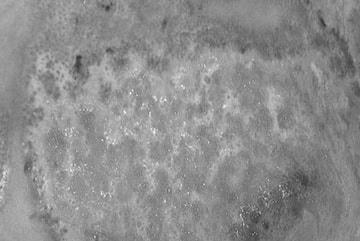

Bệnh viện Đại học Y khoa Vinh cho biết, bệnh nhân là D.T.D., nữ, 67 tuổi, trú tại Nghệ An, nhập viện khoảng đầu tháng 4 với tổn thương bỏng đã đóng vảy ngày thứ 2, diện tích 4% ở mặt trong đùi.

Sau 2 ngày, tổn thương ở chân của bệnh nhân lan rộng, đóng vảy bên ngoài và ứ dịch mủ bên trong kèm theo cảm giác đau rát, ảnh hưởng sinh hoạt hàng ngày, buộc bà D. đi khám.

Tại Bệnh viện trường Đại học Y khoa Vinh, bác sĩ Bình nhận định bệnh nhân bị bỏng hóa chất độ 2, 3 do không được sơ cứu đúng cách.

"Tổn thương đã đóng vảy nhưng thực chất vẫn lan rộng và tiếp tục tăng độ nặng. Do đó, bệnh nhân được chỉ định nhập viện và điều trị ngay", bác sĩ Bình cho biết. Sau 10 ngày điều trị, hiện tổn thương bỏng của bệnh nhân liền sẹo, không còn đau nhức. Bà D. có thể đi lại, vận động bình thường.